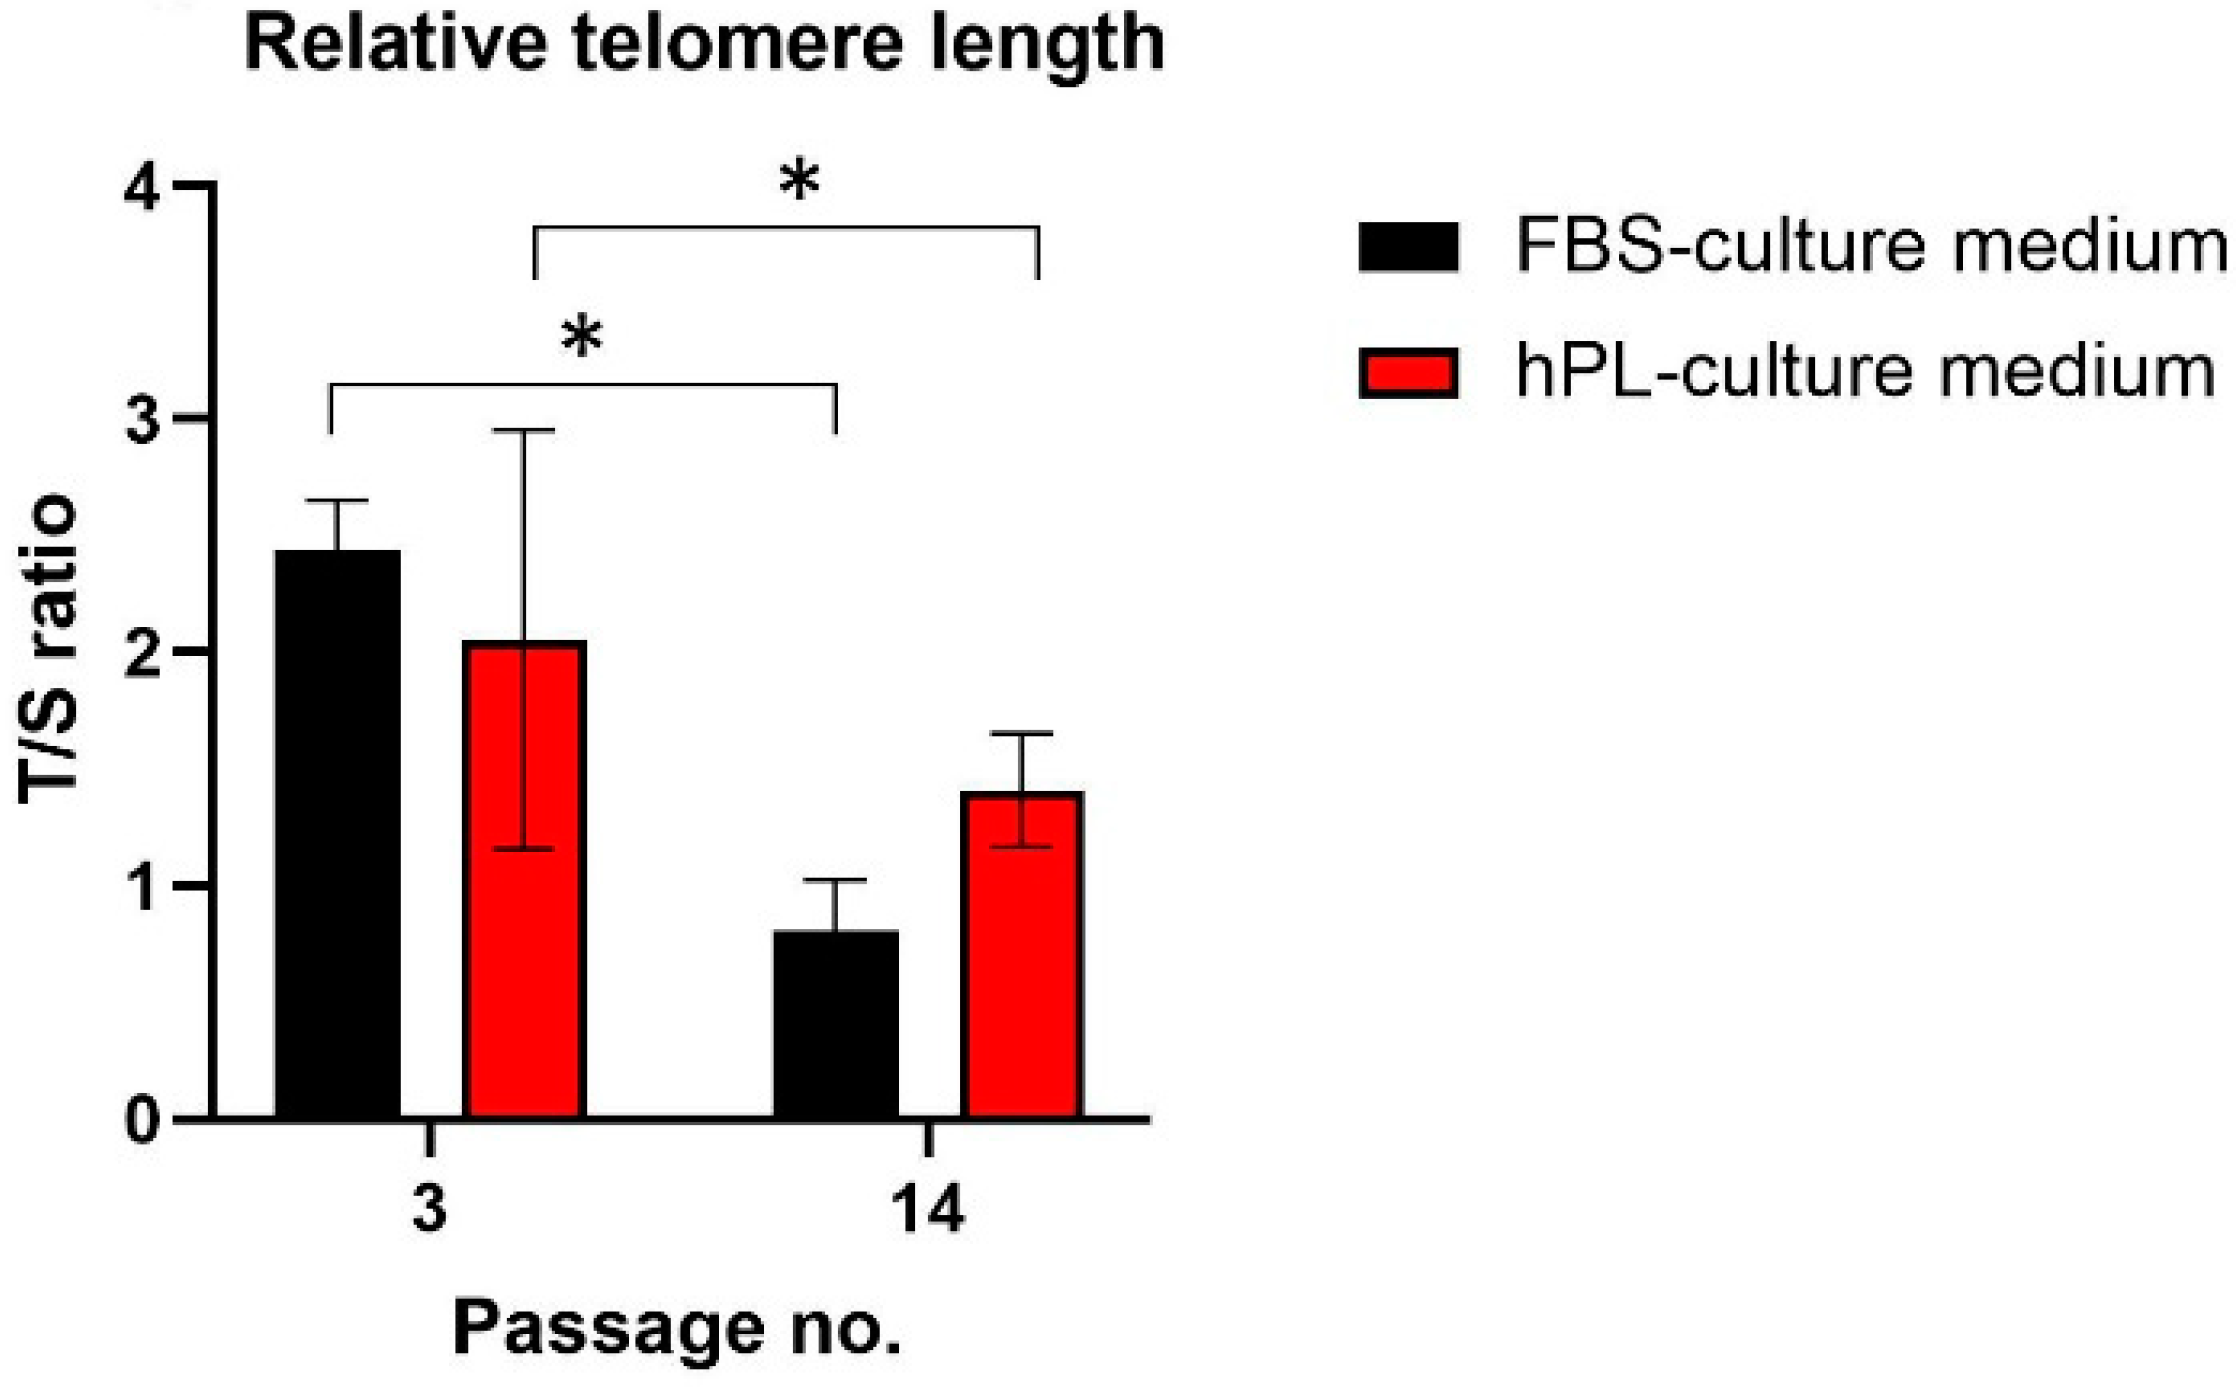

2.5. Effect on Relative Telomere Length

3.3. Effect on Relative Telomere Length